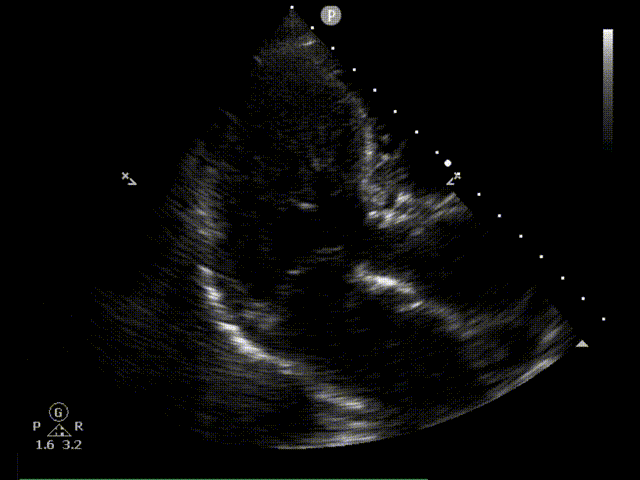

复查造影提示瓣膜固定良好,形态可,仅少量反流;复查超声提示瓣膜功能正常,平均跨瓣压差下降为11mmHg,未见明显瓣周漏;最后退出鞘管,缝合血管。